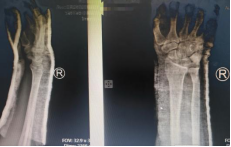

接诊的主治医师杜龙龙第一时间完成体格及X线影像检查,结果显示,右桡骨远端骨折,且骨折线已穿透关节面。关节面骨折如同精密齿轮错位,复位时哪怕1毫米的偏差,都可能留下腕关节僵硬、创伤性关节炎的后遗症。面对复杂病情,杜龙龙医师迅速联系科主任董博及副主任医师周健进行会诊。

在充分告知并获得患者及家属知情同意后,杜龙龙主治医师在董博主任和周健副主任医师现场指导下,为何先生实施手法复位。凭借扎实的解剖知识与丰富的临床经验,团队精准把控复位力度与方向,通过轻柔而稳健的操作,逐步纠正骨折端的移位与畸形。整个过程流畅高效、一气呵成。复位完成后,复查X线片显示,骨折对位对线良好,关节面恢复平整,达到理想复位标准。何先生当即感到腕部疼痛显著缓解,扭曲的手腕形态恢复正常,对治疗效果连连称赞。